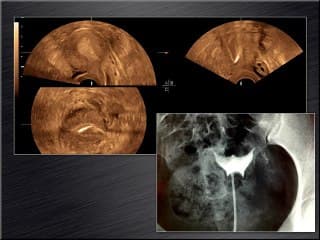

J M LEVAILLANT présente une technique révolutionnaire capable en un seul temps d'évaluer toute la fertilité féminine : J3 - J5 outre le compte es follicules antraux, l'appréciation de la cavité utérine comme dans l'hysterosonographie, l'HYCOSY permet de remplacer avantageusement la radiologie conventionnelle de l'HSG.